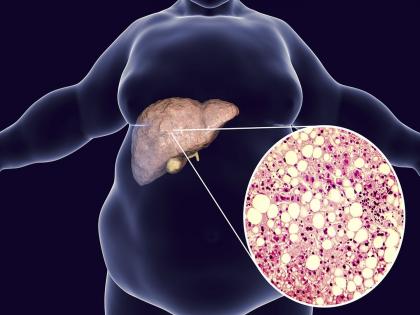

डायबिटीसचा आजार हा एक मेटाबॉलिक डिसऑर्डरचा आजार आहे. वैश्विक स्तरावर पाहिलं तर टाइप २ डायबिटीस जास्त प्रमाणात वाढत आहे. डायबिटीस हा आजार इन्सुलिन कमी झाल्या कारणाने होतो. पण जिनेव्हा युनिव्हर्सिटीमध्ये करण्यात आलेल्या एका रिसर्चनुसार, केवळ इन्सुलिन कमी असल्याने डायबिटीस हा आजार होतो असं नाही. डायबिटीस फॅटी लिव्हरमुळेही होऊ शकतो.

oद हेल्थ साइटने दिलेल्या वृत्तानुसार, अभ्यासकांनुसार, लठ्ठपणा आणि फॅटी लिव्हरमुळे इन्सुलिनची कमतरता होते. फॅटी लिव्हरमुळे हार्मोन्समध्ये जे बदल होतात, त्याने ग्लूकोज जास्त तयार होतं. ग्लूकोजच्या अधिक निर्मितीमुळे टाइप २ डायबिटीसचा धोका अधिक वाढत असतो. याचा संबंध कोणत्या हार्मोनल बदलाशी सुद्धा नाही. हा रिसर्च बायोलॉजिकल केमिस्ट्रीमध्ये प्रकाशित करण्यात आला आहे.

फॅटी लिव्हरमुळे डायबिटीसचा धोका का?

रक्तात ग्लूकोजचं प्रमाण दोन विरोधी हार्मोन द्वारे नियंत्रित केलं जातं. हार्मोन इन्सुलिन ब्लड शुगरचं प्रमाण कमी करतं आणि हार्मोन ग्लूकागन याला वाढवतं. हृदय या दोन हार्मोनच्या प्रभावात ग्लूकोजची निर्मिती आणि पुर्नवितरण करून ब्लड शुगरचं प्रमाण नियंत्रित करतं. लठ्ठ लोकांमध्ये इन्सुलिनमध्ये अडथळा निर्माण होण्याचा धोका असतो आणि त्यांच्यात यकृत पेशींमध्ये चरबी जमा करण्याची प्रवृत्ती देखील असते. याने लिव्हरध्ये फॅट लिव्हरची समस्या निर्माण होते.

अभ्यासकांचं मत आहे की, या परिवर्तनांचा मायटोकॉन्ड्रिअल फंक्शनवर प्रभाव पडू शकतो. रिसर्चमध्ये त्यांनी यकृत पेशी मायटोकॉन्ड्रिया, लठ्ठपणा आणि मधुमेह यांच्यात संबंध शोधण्याचा प्रयत्न केला. त्यांनी OPA1 नावाच्या प्रोटीनवर लक्ष केंद्रीत केलं. ज्याने मायटोकॉन्ड्रियाची संरचना कायम ठेवली जाते.